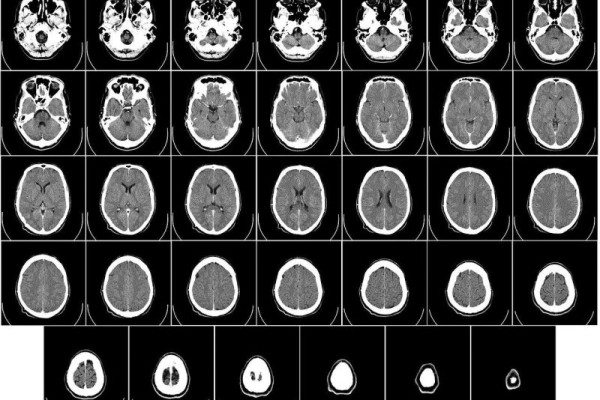

Delivering dual-targeted, immune-focused CAR T cancer therapy via a patient’s spinal fluid quickly shrank deadly brain tumors, researchers report. Image from Wikiimages/Pixabay

MRI brain scans of all six patients enrolled in the trial showed rapid tumor reductions occurring within a day or two of treatment.

The strategy seemed to work: MRI scans taken just 24 and 48 hours after CAR T delivery showed a remarkable shrinkage of tumors.